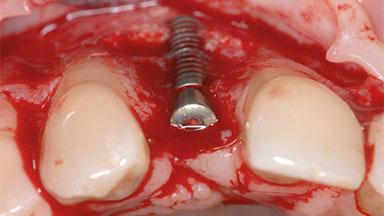

Removal of a Malpositioned Implant and Direct New Implant Placement with Simultaneous Contour Augmentation using GBR

Daniel Buser, Urs C Belser

A 35-year old female patient was referred to the Department of Oral Surgery and Stomatology at the University of Bern, Switzerland, for examination of an implant site that had exhibited clinical signs of slightly delayed wound healing. In addition, the referring clinician found no evidence for a facial bone wall when she raised a flap to gain access to the implant for abutment connection. Four months earlier, she had inserted a bone-level implant in a single-tooth gap, where the lateral incisor had been extracted due to a chronic periapical lesion on the mesial aspect of the root. Implant placement was combined with simultaneous bone augmentation using deproteinized bovine bone mineral (DBBM, Bio-Oss®; Geistlich, Wolhusen, Switzerland) and a collagen membrane (Bio- Gide®; Geistlich), followed by primary wound closure. The patient also provided the postsurgical radiograph that displayed the implant with a 3.5-mm healing cap.